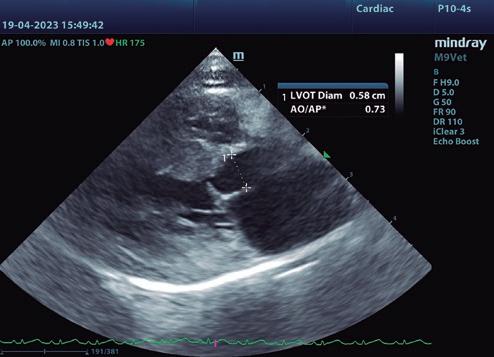

• Modo B: en la proyección paraesternal derecha eje largo, se observó un jet de regurgitación mitral con dirección posterior y SAM (figura 3). En el eje corto derecho a la altura de la base cardiaca se observó un ratio atrio izquierdo/aorta (AI/Ao) de 1,92 (>1,6 se considera dilatación AI) (figura 4). Además, se observó hipertrofia de la pared del septo interventricular (SIV) de 7,6 mm y la pared libre del ventrículo izquierdo (PLVI) la 8,4 mm (hipertrofia >6 mm) (figura 5).

7. Proyección paraesternal izquierda cinco cámaras. Mediante Doppler color, se observa el flujo turbulento hacia el TSVI y hacia el AI. Se toma la velocidad del flujo que discurre a través del TSVI, generando un gradiente de presión de 83,36 mmHg.

Para el diagnóstico de fenotipo hipertrófico, la gold estándar es la ecocardiografía. Aunque no hay una medida mundialmente aceptada para un valor normal o anormal de grosor de la pared, un aumento focal o difuso por encima de 6 mm (Fuentes et al. 2020) confirma el diagnóstico. Un AI/ Ao >1,6, justifica la presencia de ICC. En nuestro caso, el diagnóstico de fenotipo hipertrófico, se sustenta por el aumento del grosor de la pared del VI (7,6 mm en modo B y 7,8 mm en modo M) y la ICC, por el del AI/Ao (1,92).